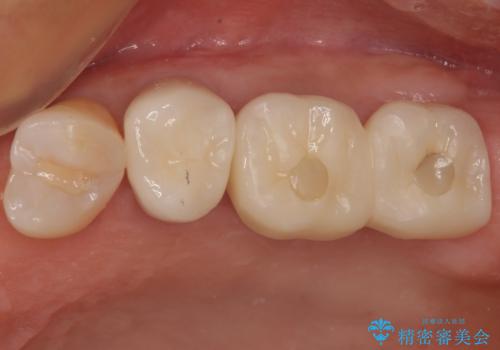

銀歯をセラミックにしたい オールセラミッククラウン

担当医 有澤哲郎